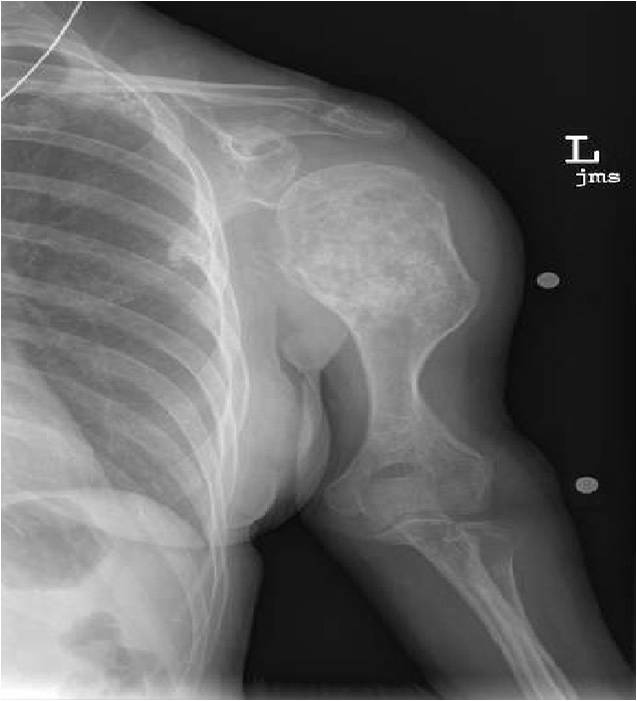

Plain X-Ray:

- Geographic lytic lesion

- Central often metaphyseal in long bones

- Expansile remodeling with thinned cortex

- Chondroid matrix with calcifications in majority of tumors

Metaphyseal Tumor, Heavy Calcifications, Ring and Arc Pattern of Calcifications, Minimal Endosteal Scalloping, No Cortical Destruction, No Periosteal Reaction, No Cortical Destruction, No Soft Tissue Component

Metaphyseal Tumor, Heavy Calcifications, Ring and Arc Pattern of Calcifications, Minimal Endosteal Scalloping, No Cortical Destruction, No Periosteal Reaction, No Soft Tissue Component